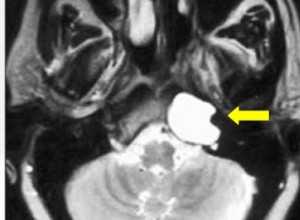

МРТ головного мозга. На мрт в аксиальной плоскости отмечается объемное образование внутреннего слухового прохода слева (стрелка), с четкими и неровными контурами, деформирующее окружающие структуры. После внутривенного введения парамагнитного контрастного вещества отмечается интенсивное и неоднородное его накопление образованием (изображение справа) — невринома.